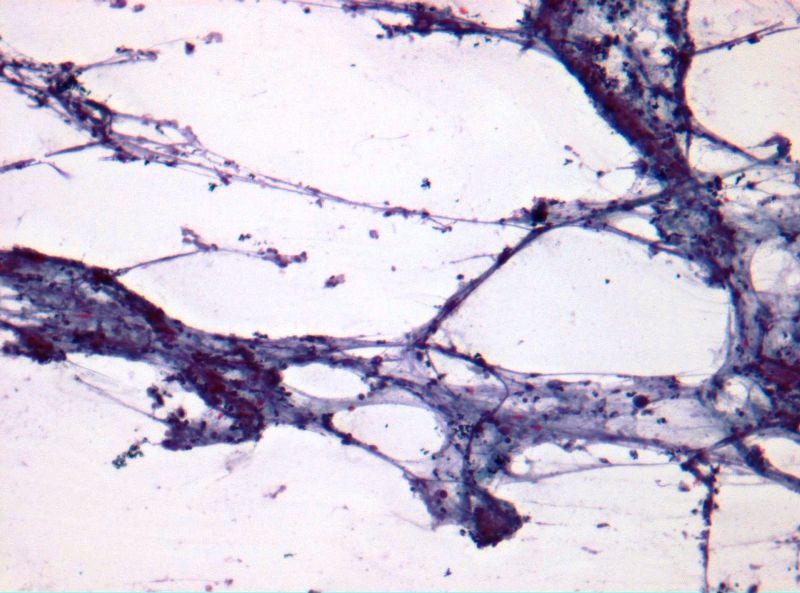

Dra. Mª Rosa Bella (patòleg) i Dr. Mario Prenafeta (radiòleg).

Hospital Universitari Parc Tauli Sabadell

Dona de 59 anys, fumadora de 15-20 cigarretes/dia fins fa 10 anys, sense altres hàbits tòxics destacables, amb antecedents patològics de Diabetes Mellitus tipus I que tracta amb insulina, Hipertensió arterial, i dislipèmia. Consulta per cuadre progressiu desde fa 5-6 mesos d'anosmia, cefalees hemicraneals esquerres, hipoestesia d'hemicara esquerra, epistaxis esquerres que es fan diàries, visió borrosa amb diplòpia, i tumefacció cervical esquerra. A l'exploració física s'observa exoftalmos esquerre i adenopaties laterocervicals esquerres indurades, i a l'estudi ORL s'observa lesió polipoidea eritematosa a fossa nasal provinent de meat superior esquerre. Es realitzen diverses proves de Diagnòstic per la imatge, i es realitzen simultàniament punció aspirativa i biòpsia de la lesió a fossa nasal. S'adjunten imatges de la RNM cranial, i de punció aspirativa.